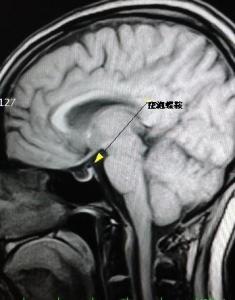

空泡蝶鞍磁共振

垂体mri示空泡蝶鞍(箭头)